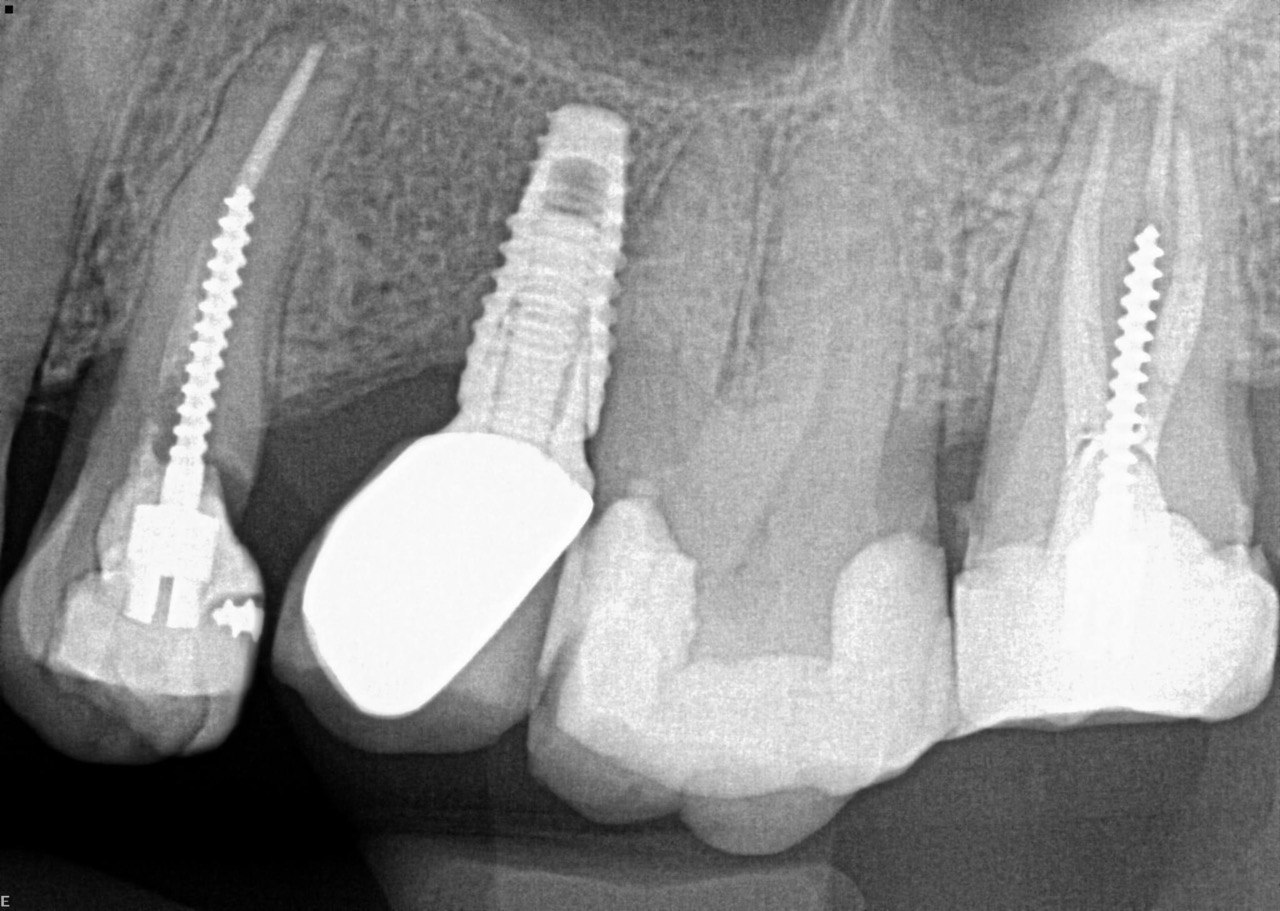

16. What condition can be seen in distal of tooth # 3.7?

17. What condition can be seen in distal surface of the tooth # 4.7?

18. What condition can be seen in buccal surface of the teeth # 1.1 ans 2.1?

19. What is the condition on the distal surface of the tooth # 3.7?

20. what condition can be seen in buccal surface of 4.4 and 4.5?

21. what condition can be seen on the distal surface of the tooth #4.1?

22. what condition can be seen on the mesial surface of the tooth #4.1?

23. What condition can be seen on the distal surface of the tooth #1.2?